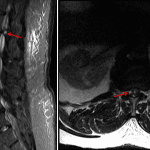

- 5 mm T2/STIR hyperintense extradural structure on the right at the level of L1-L2 extending medially from the facet joint, which results in severe spinal canal stenosis and mass effect on the conus

- Increased T2/STIR signal centrally in the conus at the level of L1-L2

- Synovial cyst with cord compression

5 mm synovial cyst on the right at L1-L2 which severely narrows the spinal canal and exerts mass effect on the conus. T2/STIR signal hyperintensity in the conus at this level concerning for edema.